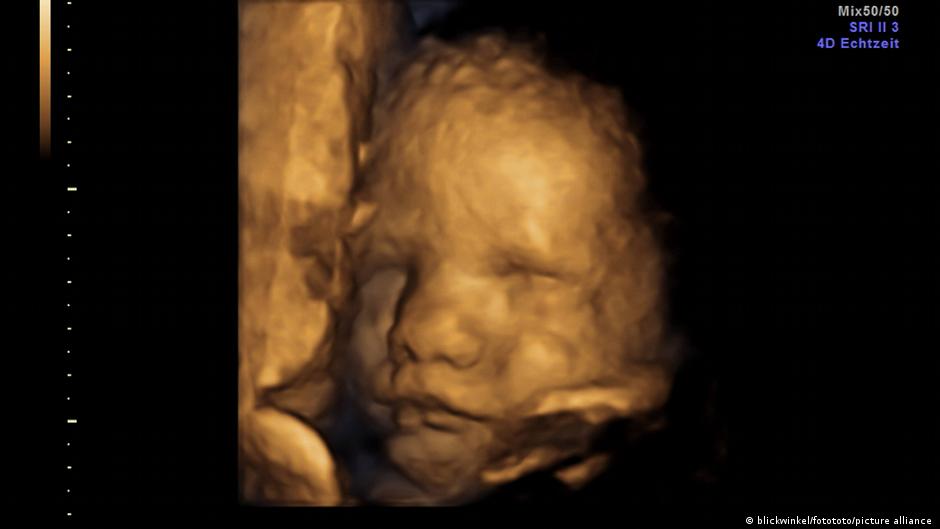

गर्भ में भी बच्चों के चेहरे गाजर के स्वाद से खिल उठते हैं

नई दिल्ली, 22 सितंबर। उत्तरपूर्वी इंग्लैंड में दुरहम यूनिवर्सिटी के रिसर्चरों का कहना है कि उनकी खोज से पहली बार इस बात के सीधे सबूत मिले हैं कि बच्चे जन्म से पहले ही अलग गंध और स्वाद को लेकर अलग तरह की प्रतिक्रिया देते हैं. वैज्ञानिकों की एक टीम ने 100 गर्भवती महिलाओं के 4डी अल्ट्रासाउंड स्कैन का अध्ययन किया और यह पता लगाया कि गाजर के स्वाद के संपर्क में आने वाले बच्चों के चेहरे पर हंसी दिखाई पड़ी. इसी तरह जिन बच्चों को गहरे रंग वाली पत्तेदार गोभी का जायका मिला उनके चेहरे रुआंसे हो गये.

पोस्ट ग्रेजुएट रिसर्चर बेयजा उस्तुन का कहना है, "कई अध्ययनों से यह पता चला था कि बच्चे गर्भ में ही स्वाद और गंध को जान सकते हैं लेकिन यह नतीजा उनके जन्म के बाद की जानकारियों से निकाला गया था. हमारी स्टडी में पहली बार जन्म से पहले ही उनकी प्रतिक्रियाओं को देखा गया है.